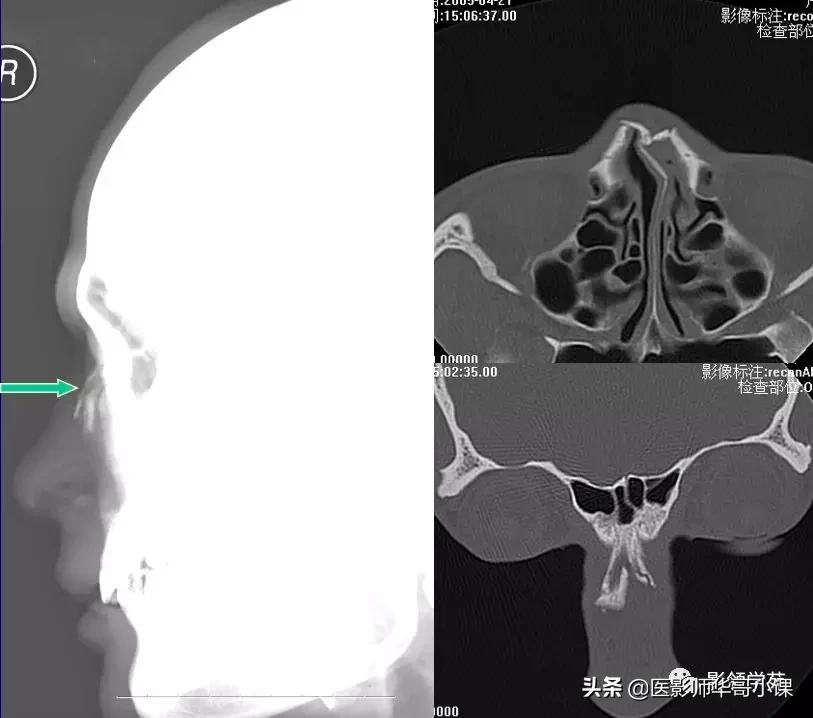

X线平片:侧位

HRCT

- 横断面:听眶下线

- 冠状面:鼻骨长轴平行线

- 层厚:1~2mm

鼻骨正常侧位

鼻骨横断面HRCT

鼻骨冠状面HRCT